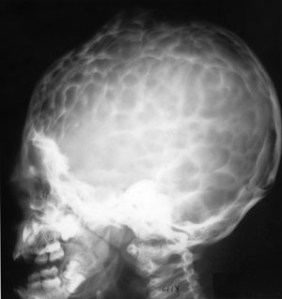

SIGNO DEL BRONCE BATIDO

El nombre de cráneo en bronce batido (o también cobre batido) hace referencia al aspecto de los huesos craneales con marcado aumento del patrón de circunvoluciones. La causa está en el aumento de la presión intracraneal que puede ser debido al cierre precoz de las suturas (craneosinostosis), hidrocefalia obstructiva, masas intracraneales o hipofosfatasia.

Afortunadamente, este signo es difícil de ver en la actualidad.

La imagen está cedida por el Dr. Leonard E Swischuk, quien ha otorgado el permiso para su publicación en esta web. Mi agradecimiento por su amabilidad.